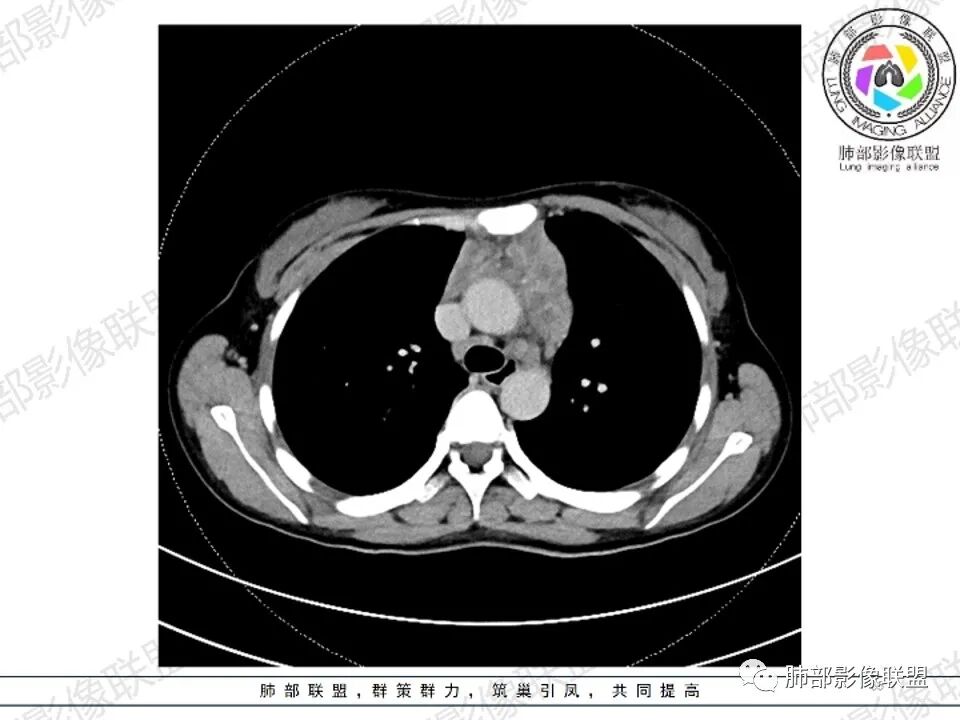

2.影像显示前纵隔不规则块状影,依势贴附心脏大血管旁,密度不均,边界不甚清楚,有结节融合感。

3.病灶轻度不均匀强化,可见血管穿行,散在液性低密度区。

4.双侧腋窝区见增大淋巴结,边界清楚。

1.年轻女性,前纵隔不规则块状影,密度不均,边界不甚清楚,有结节融合感,轻度不均匀强化,可见血管穿行,最常见最符合的无疑是淋巴瘤!